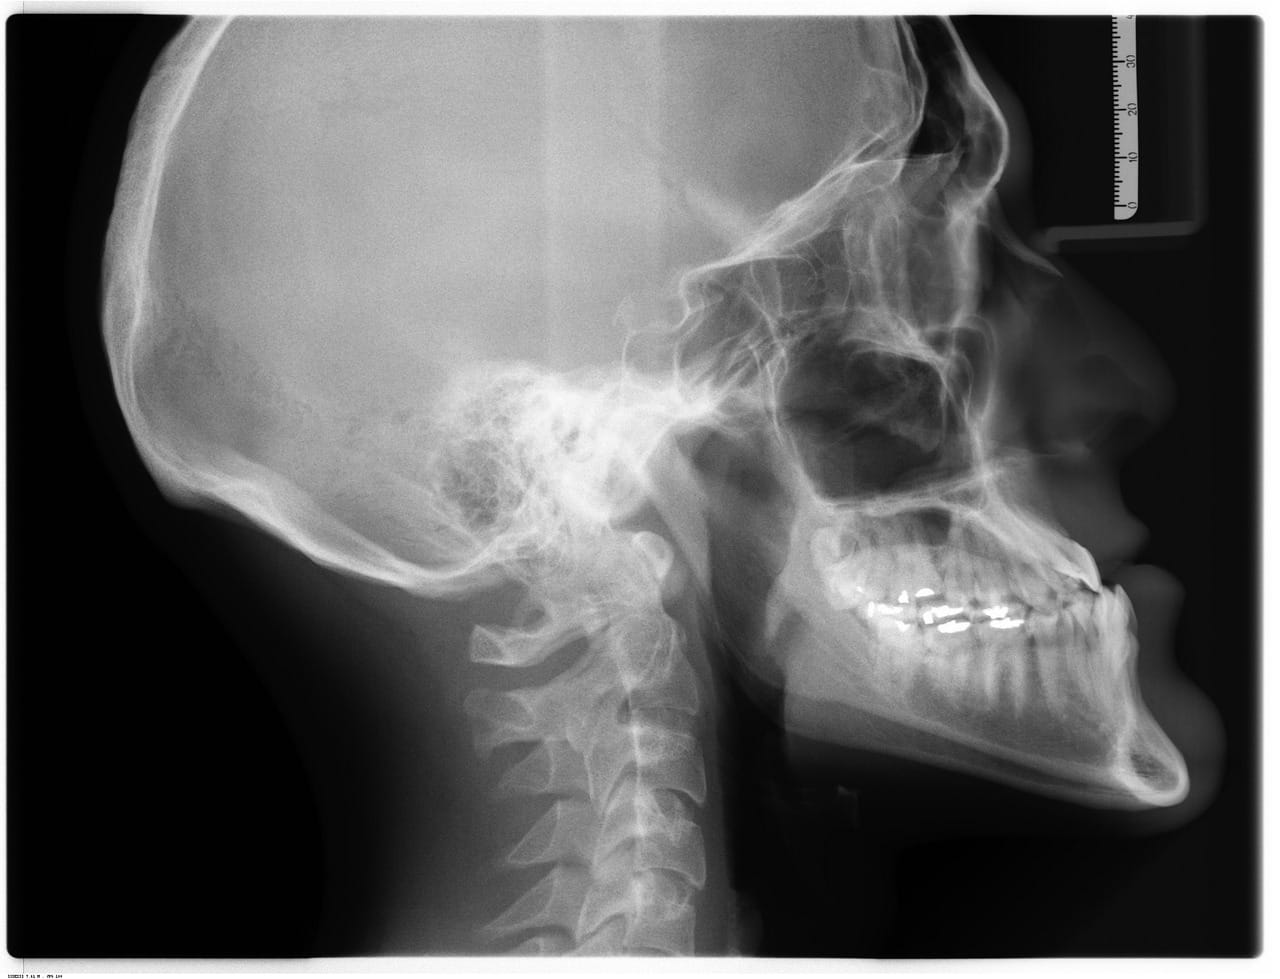

Undersøkelse – Hva ser vi etter?

En grundig anamnese og undersøkelse er avgjørende for å stille riktig diagnose og utelukke andre årsaker til smerte i arm og hånd – noen av dem kan være mer alvorlige.

Undersøkelse av nakke og skulder for å identifisere bidragende faktorer